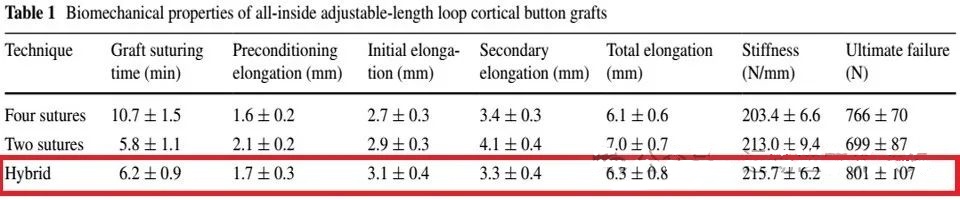

在ACL全内重建术中,对于移植物的编织方法也有很高的技术要求。于传统肌腱的简单编织缝合不同,由于全内移植物两端均使用悬吊固定,因此需要采用埋结编织法,但笔者更喜欢一种杂交改良的埋结编织法(Raul Mayr, KSSTA)。

上述的C法就是作者改良的埋结编织缝合法

测试表明,这种方法不仅缝合速度超快,而且生物力学超强